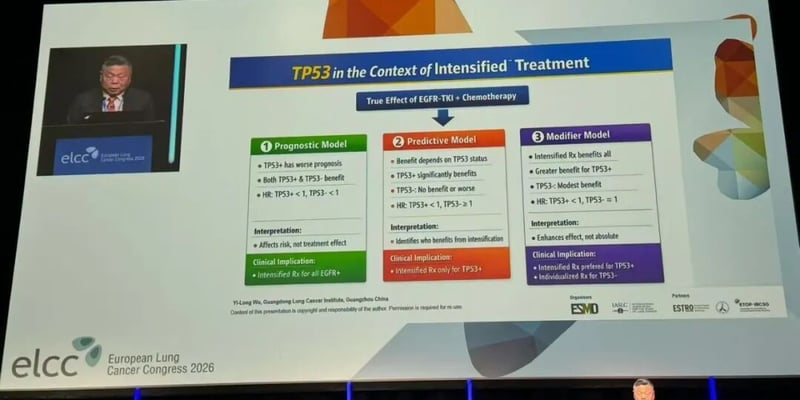

EGFR突变非小细胞肺癌在奥希替尼等EGFR-TKI后进展,下一步治疗常陷入选择困难。PD-L1×VEGF-A双抗联合化疗、HER3 ADC联合抗血管生成方案正在给耐药患者带来新的PFS、缓解率和安全性线索。 Read More... "EGFR突变肺癌TKI耐药后怎么办:双抗与HER3 ADC新方案"